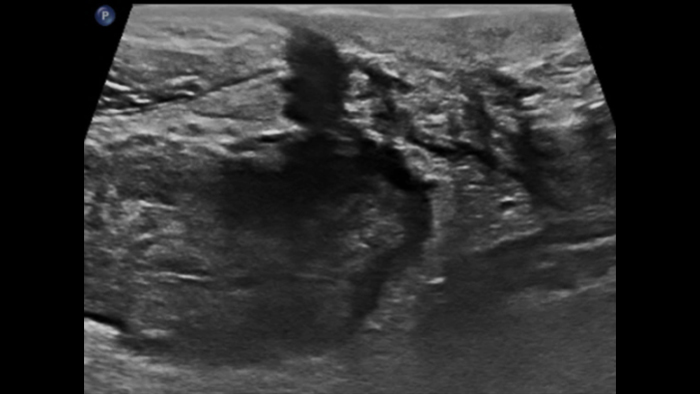

Dans les formes tardives de la maladie de Crohn, la différenciation des couches a tendance à s’estomper avec le développement d’une fibrose transmurale et devient ensuite invisible. La scléro-lipomatose du tissu adipeux mésentérique adjacent est hypertrophique et a un aspect en verre dépoli. Les fistules actives se présentent sous forme de trajets hypoéchogènes linéaires entre la paroi digestive et la scléro-lipomatose.

Fistula Adjacent fat hypoechoic course